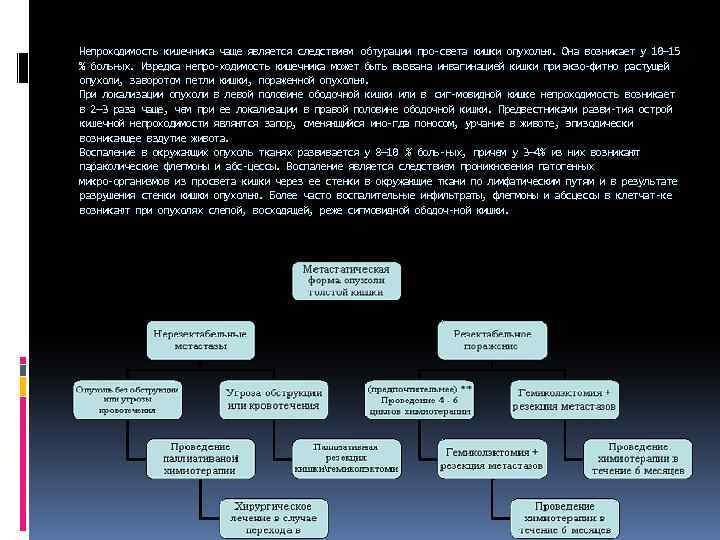

Непроходимость кишечника чаще является следствием обтурации про света кишки опухолью. Она возникает у 10— 15 % больных. Изредка непро ходимость кишечника может быть вызвана инвагинацией кишки при экзо фитно растущей опухоли, заворотом петли кишки, пораженной опухолью. При локализации опухоли в левой половине ободочной кишки или в сиг мовидной кишке непроходимость возникает в 2— 3 раза чаще, чем при ее локализации в правой половине ободочной кишки. Предвестниками разви тия острой кишечной непроходимости являются запор, сменяющийся ино гда поносом, урчание в животе, эпизодически возникающее вздутие живота. Воспаление в окружающих опухоль тканях развивается у 8— 10 % боль ных, причем у 3— 4% из них возникают параколические флегмоны и абс цессы. Воспаление является следствием проникновения патогенных микро организмов из просвета кишки через ее стенки в окружающие ткани по лимфатическим путям и в результате разрушения стенки кишки опухолью. Более часто воспалительные инфильтраты, флегмоны и абсцессы в клетчат ке возникают при опухолях слепой, восходящей, реже сигмовидной ободоч ной кишки.

При наличии неудалимой опухоли или отдаленных метастазов произво дят паллиативные операции, направленные на предупреждение непроходи мости кишечника: паллиативные резекции, наложение обходного илео трансверзоанастомоза, трансверзосигмоанастомоза и др, или накладывают колостому. Химиотерапия в послеоперационном периоде не уве личивает продолжительность жизни. Оптимальная схема лекарственной те рапии, так же как ценность пред и послеоперационной рентгенотерапии, не установлена.